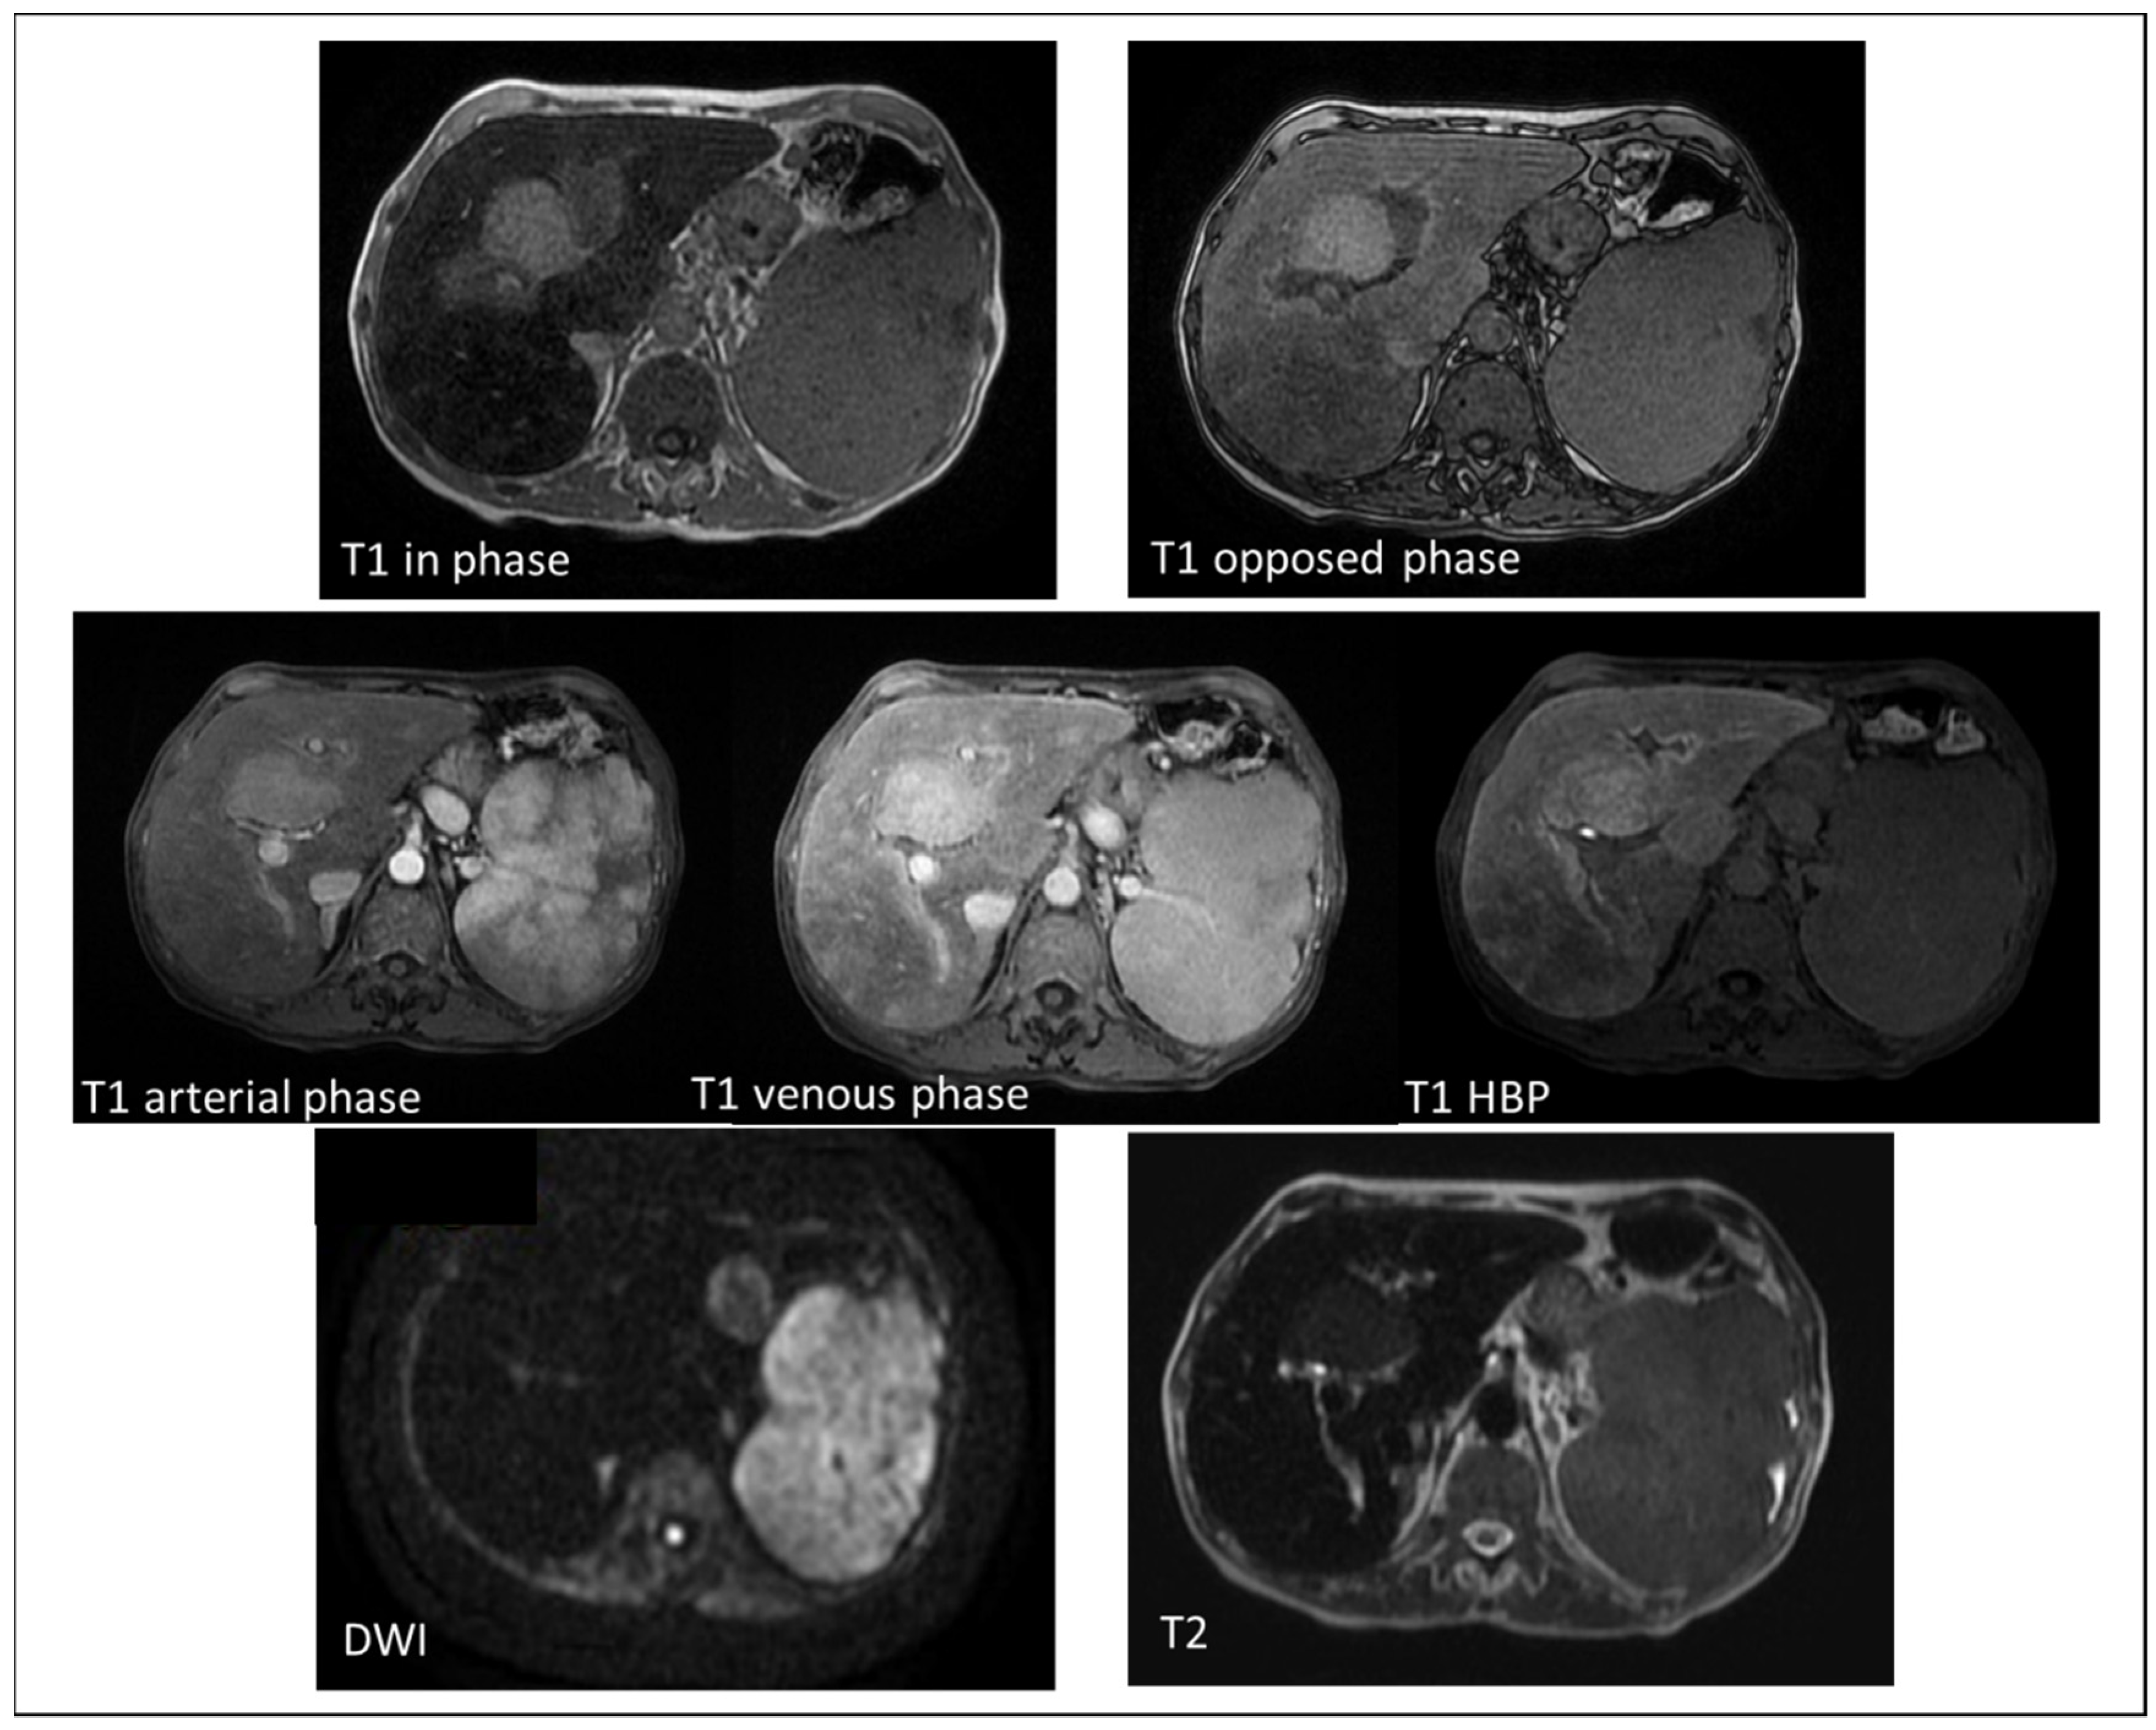

4.2. Extramedullary Hematopoiesis

4.3. Adenoma (Steroid Treatment in Case of Anemia, such as Fanconi)